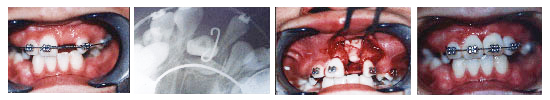

牙齿移植